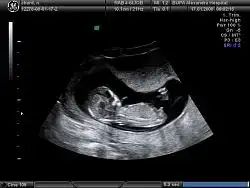

Masallah cnm erkek bnce çikintı dik bide bas popo uzunluk oranı erkek fikrine kapılmma ndn oldu

erkek erkek kesin...

Cnm o gozuken bacak deilse erkek sanırım kaç haftlıktı doktor bişe demedimi

Dr kesinlikle kiz dedi

Demekki o gozuken bacakmiş :)